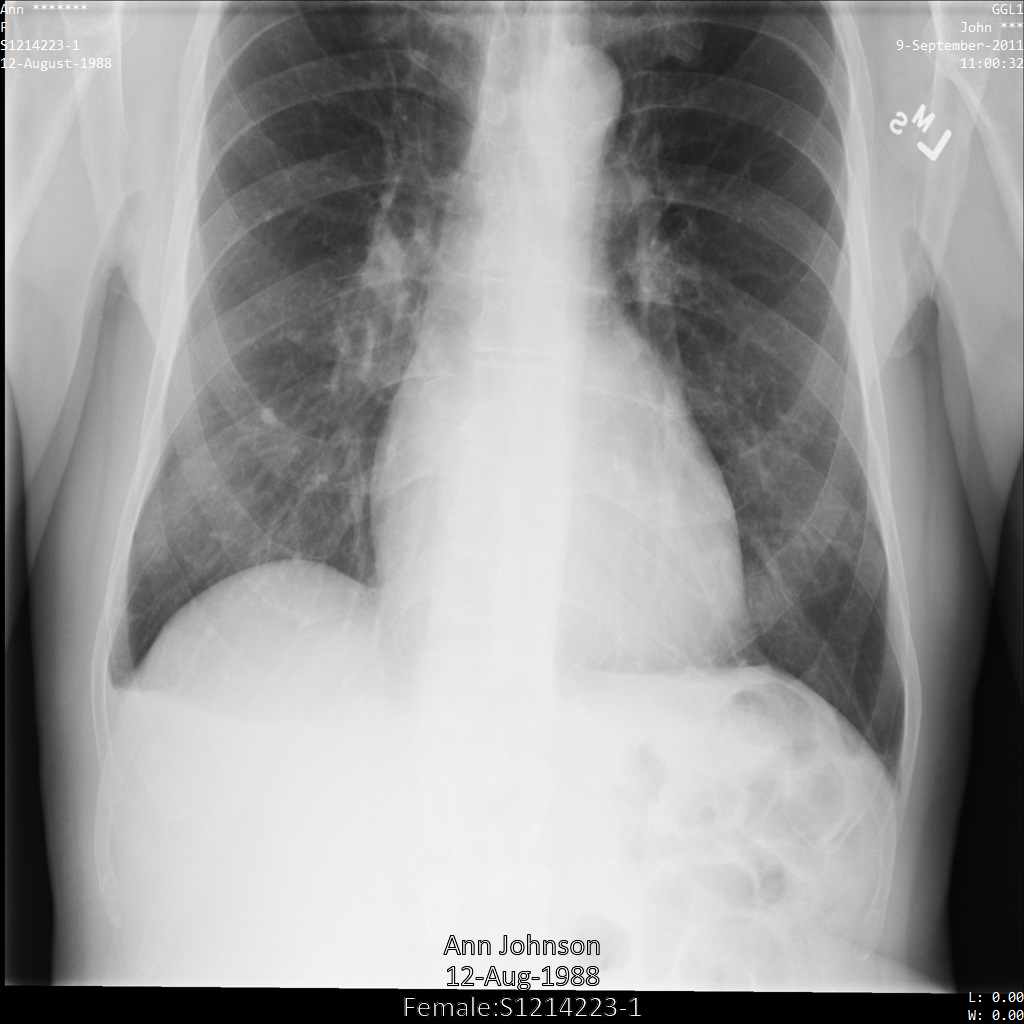

Une fois envoyée à l'API Cloud Healthcare à l'aide du profil de filtre de tag ATTRIBUTE_CONFIDENTIALITY_BASIC_PROFILE, l'image apparaît comme suit. Les métadonnées affichées dans les angles supérieurs de l'image ont été masquées, mais les données de santé incrustées en bas de l'image reste affichées.

Pour supprimer également le texte incrusté, consultez la section Masquer le texte incrusté dans les images.